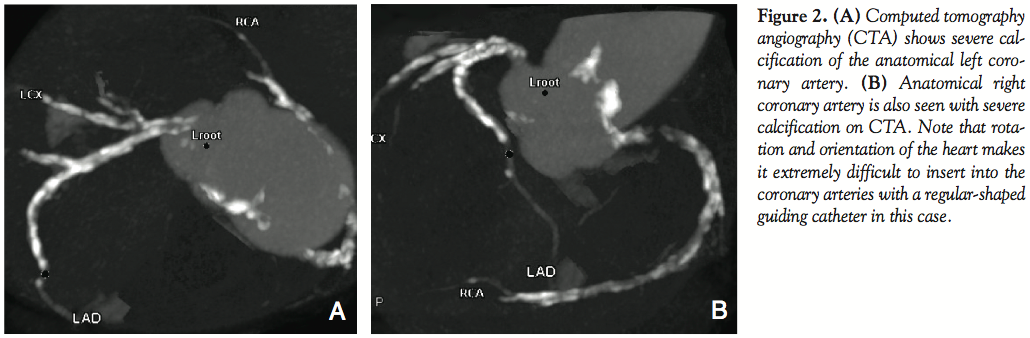

cannulation, was used for the anatomical RCA (left-sided), which revealed that the RCA had an atheromatous stenosis at the ostia. Cannulation for the anatomical left coronary artery (LCA; right-sided) using Judkins left 4 was also difficult, even effectually shaped. Stenosis at the distal left main and the ostial left anterior descending coronary artery (LAD) was ambiguous because of the insufficient cannulation for LCA. Bypass surgery would be suggested if the stenosis was at the anatomical left main. To determine the course to be taken, we performed 64-slice multidetector computed tomography. It showed dextrocardia with severely calcified coronary arteries (Figures 2A and 2B). As a result. stenosis was difficult to diagnose because of the severe calcification. On day 5, coronary catheterization was carried out again. A 6 Fr sheath was inserted at the right radial artery. An Ikari left 3.0 Heartrail II guiding catheter (Terumo Corporation) was engaged to the anatomical LCA. The engagement for LCA was better than Judkins left catheter and so better angiography was performed (Figures 3A and 3B). Using intravascular ultrasound (IVUS; Atlantis Pro, Boston Scientific), minimal lumen diameter was 2.42 × 3.18 mm (minimal lumen diameter, 6.15 mm2) at the LAD ostia (Figure 3C). Based on the angiography and IVUS findings, we chose PCI for the RCA ostial lesion, not bypass surgery. The same Ikari left 3.0 guiding catheter was engaged to the anatomical RCA (Figure 4A); the catheter engaged nicely, but back-up was not sufficient for the calcified lesion, after a Runthrough guidewire (Terumo Corporation) was passed through the lesion. Insertion of a Grandslam guidewire (Abbott Vascular) as a parallel wire proved satisfactory. Predilatation was performed with a 2.5 mm Hiryu balloon (Terumo Corporation) at 12 atm. A 3.5 × 15 mm Vision stent (Abbott Vascular) was then deployed to the ostial lesion (Figure 4B). Postdilatation was done with a 3.0 × 10 mm Powered Lacross balloon (Goodman) at 24 atm. This gave an excellent final angiographic result, and her angina attack disappeared postintervention (Figure 4C).